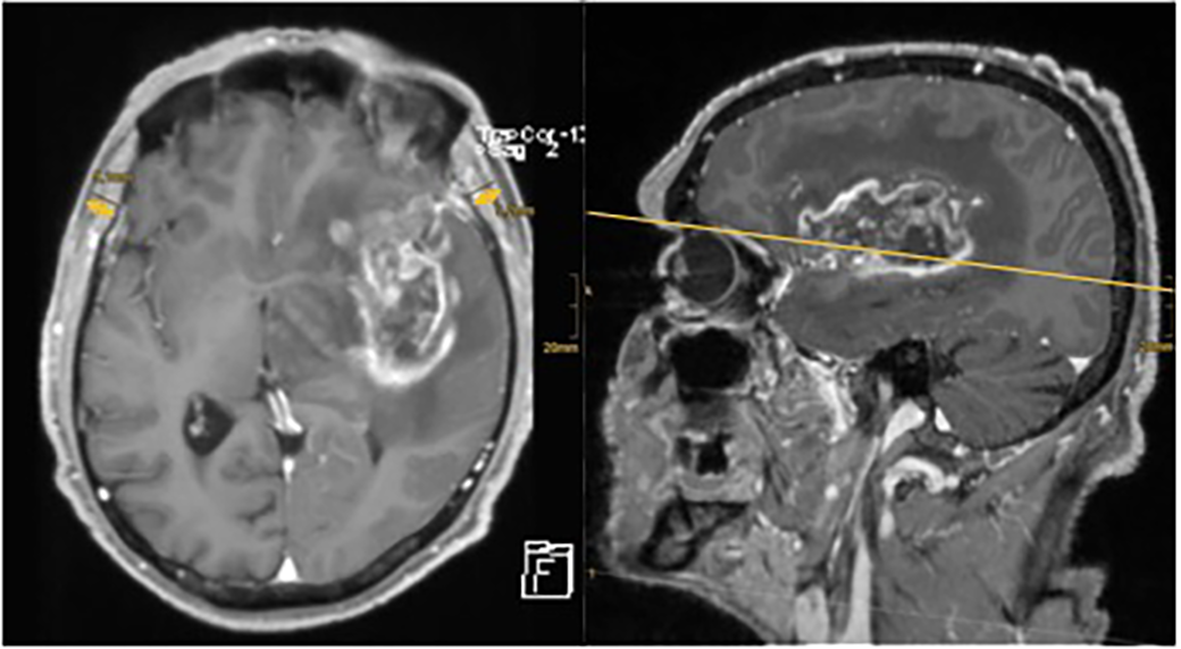

To assess TMT, measurements were taken in analogy to previous studies in this field (21–23): in the axial plane of preoperative T1-weighted contrast-enhanced MRI, TMT was measured perpendicularly to the long axis of the temporal muscle—from its inner to outer margin, not including the fascia. A landmark for craniocaudal orientation was the roof of the orbit, and for frontal–occipital orientation, we aimed for the Sylvian fissure (see Figure 1). Mean TMT was then calculated by adding left and right side TMT measurements of each patient and dividing the result by two.

Figure 1 Axial and sagittal MRI images of one of the neuro-oncological database’s patient. There is a large contrast enhancing tumor visible in the left frontotemporal hemisphere. TMT has been measured on the axial plane using the Sylvian fissure and orbital roof as reference points. The arrows indicate the extent of TMT measurement.

Figure 1 shows an example of TMT measurement in contrast-enhanced axial and sagittal T1-weighted MRI scans of a patient with HGG of our cohort.